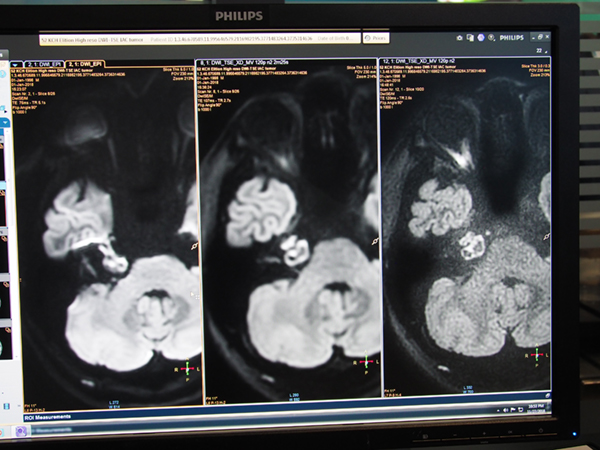

常に進化を続けるMRIアプリケーションも,新しいアプリケーションが複数提供されている。“Diffusion TSE XD”は,EPIベースでの撮像により磁化率の影響で歪みやすかった従来のDWIに対し,TSEベースで撮像することで歪みの少ない画像を取得するアプリケーションである。空気との境目で歪みやすい内耳なども形状の歪みなく撮像できることに加え,体動補正技術“MultiVane”を併用できるため,よりシャープな画像を得ることができる。

従来のDWI EPI(左),“Diffusion TSE XD”(中央),高空間分解能の“Diffusion TSE XD”(右)